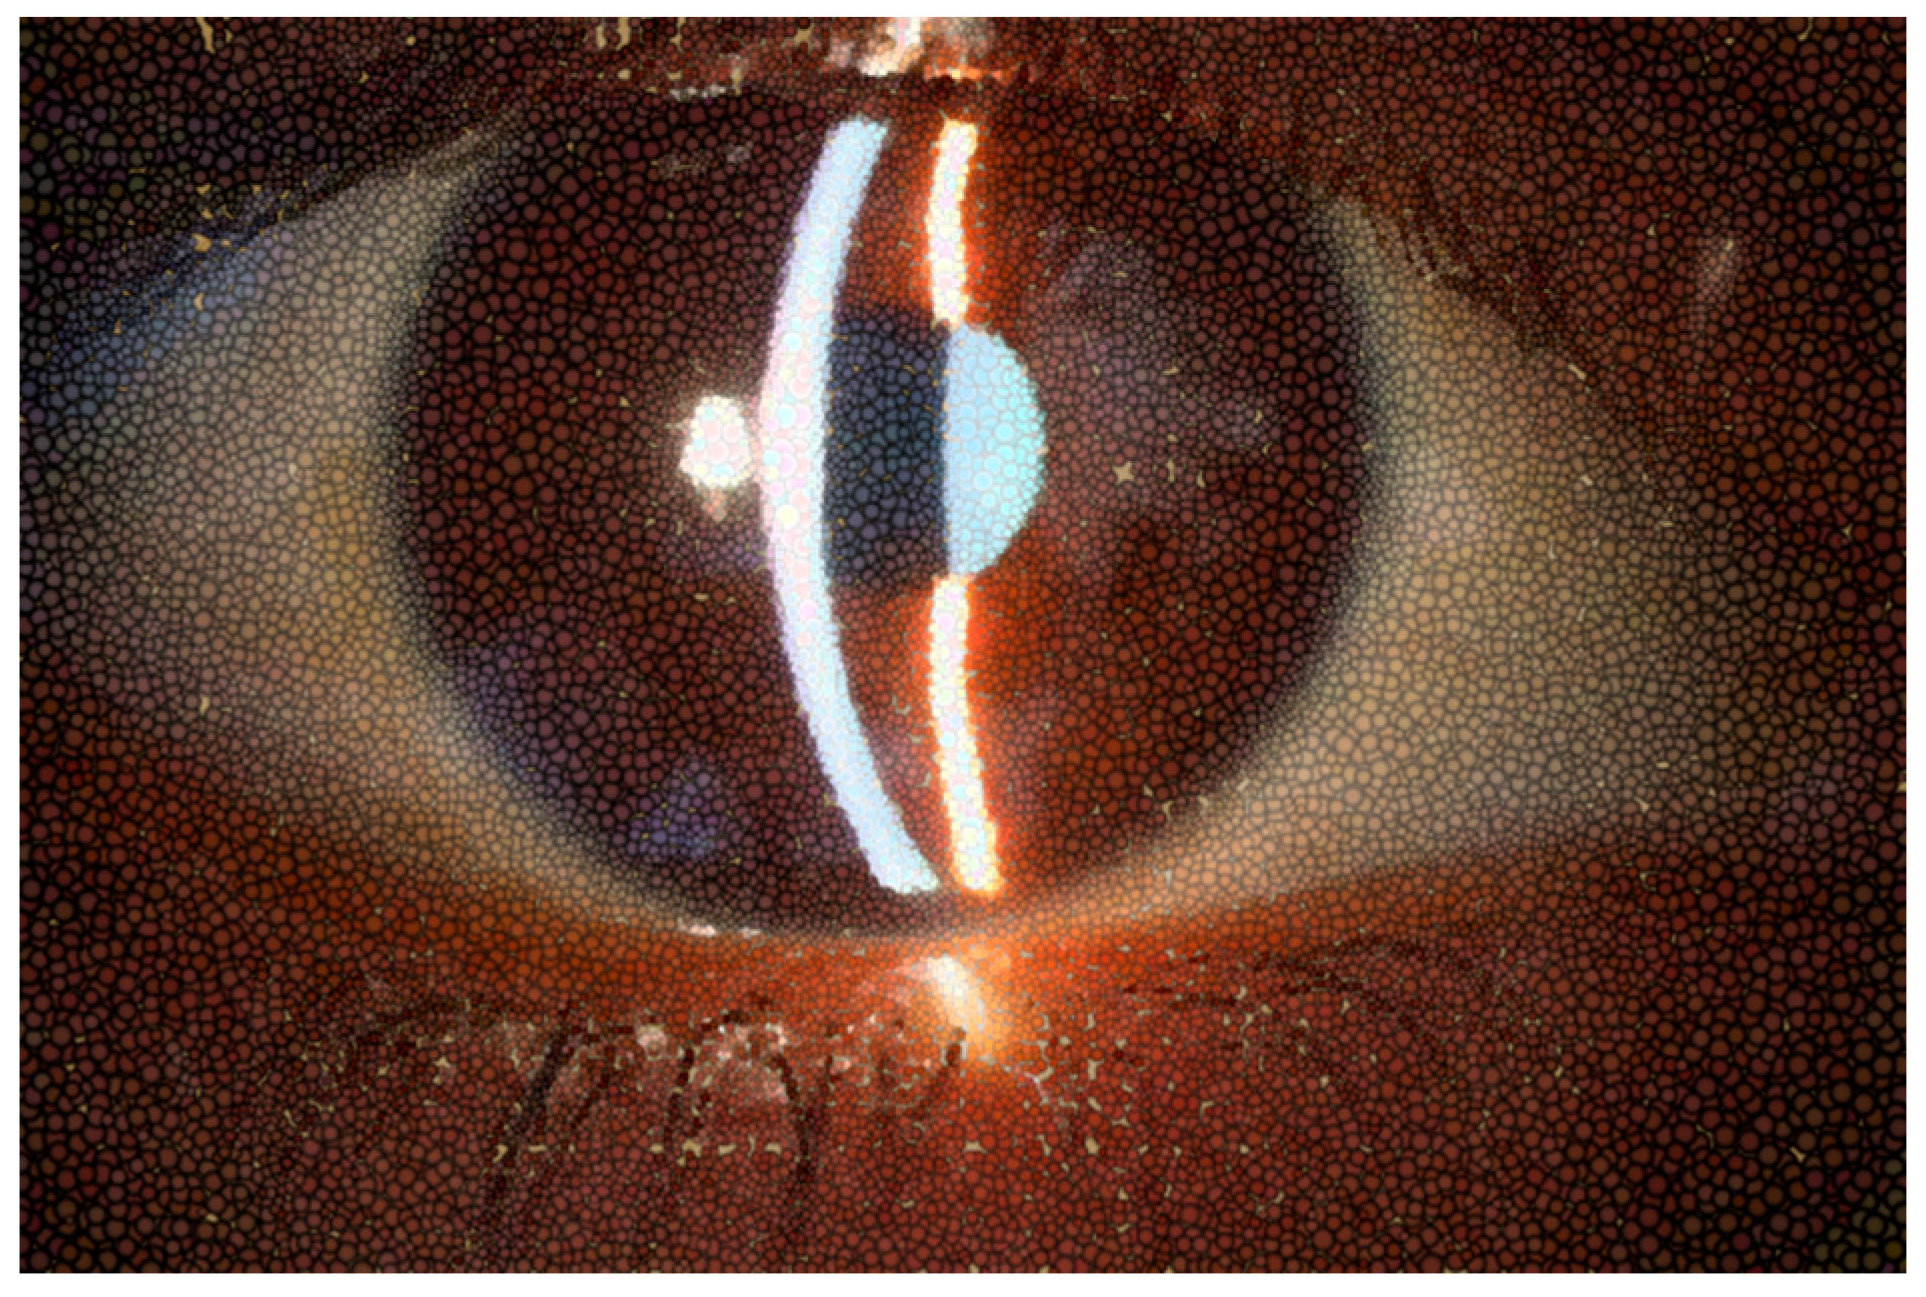

Figure 1. Normal appearance of precorneal tear film photographed with slit lamp or biomicroscope.